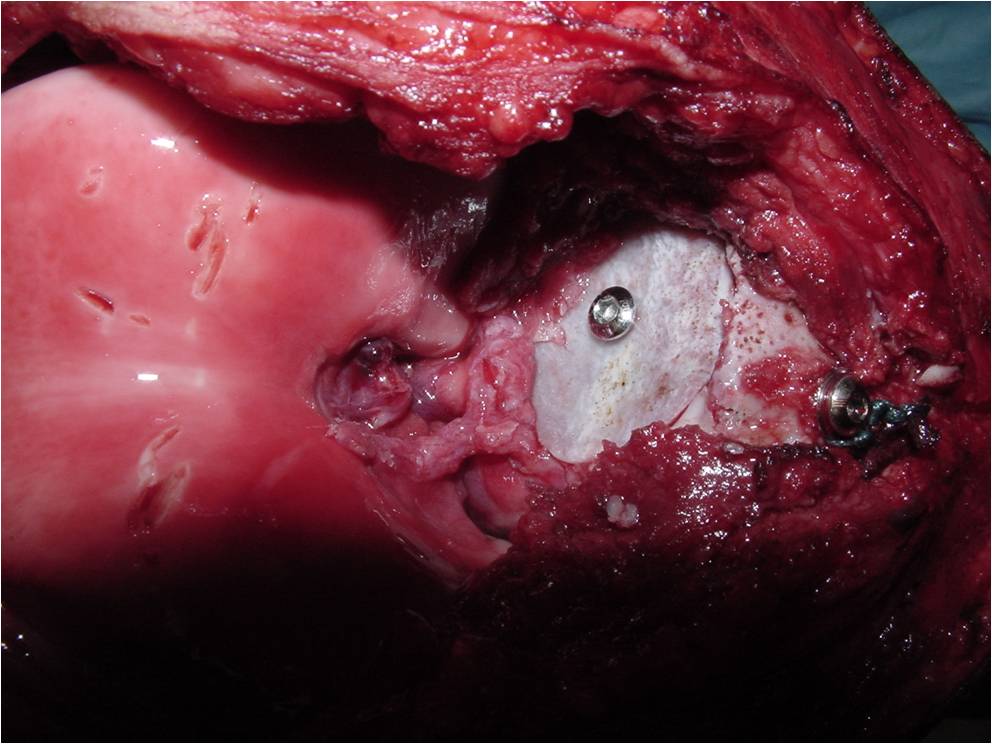

General Information Enchondroma is a benign indolent intramedullary hyaline cartilage neoplasm Accounts for 10% of all benign osseous tumors Limited growth, most lesions are less than 5 cm in maximal dimension Bones grow from a cartilaginous growth plate that...